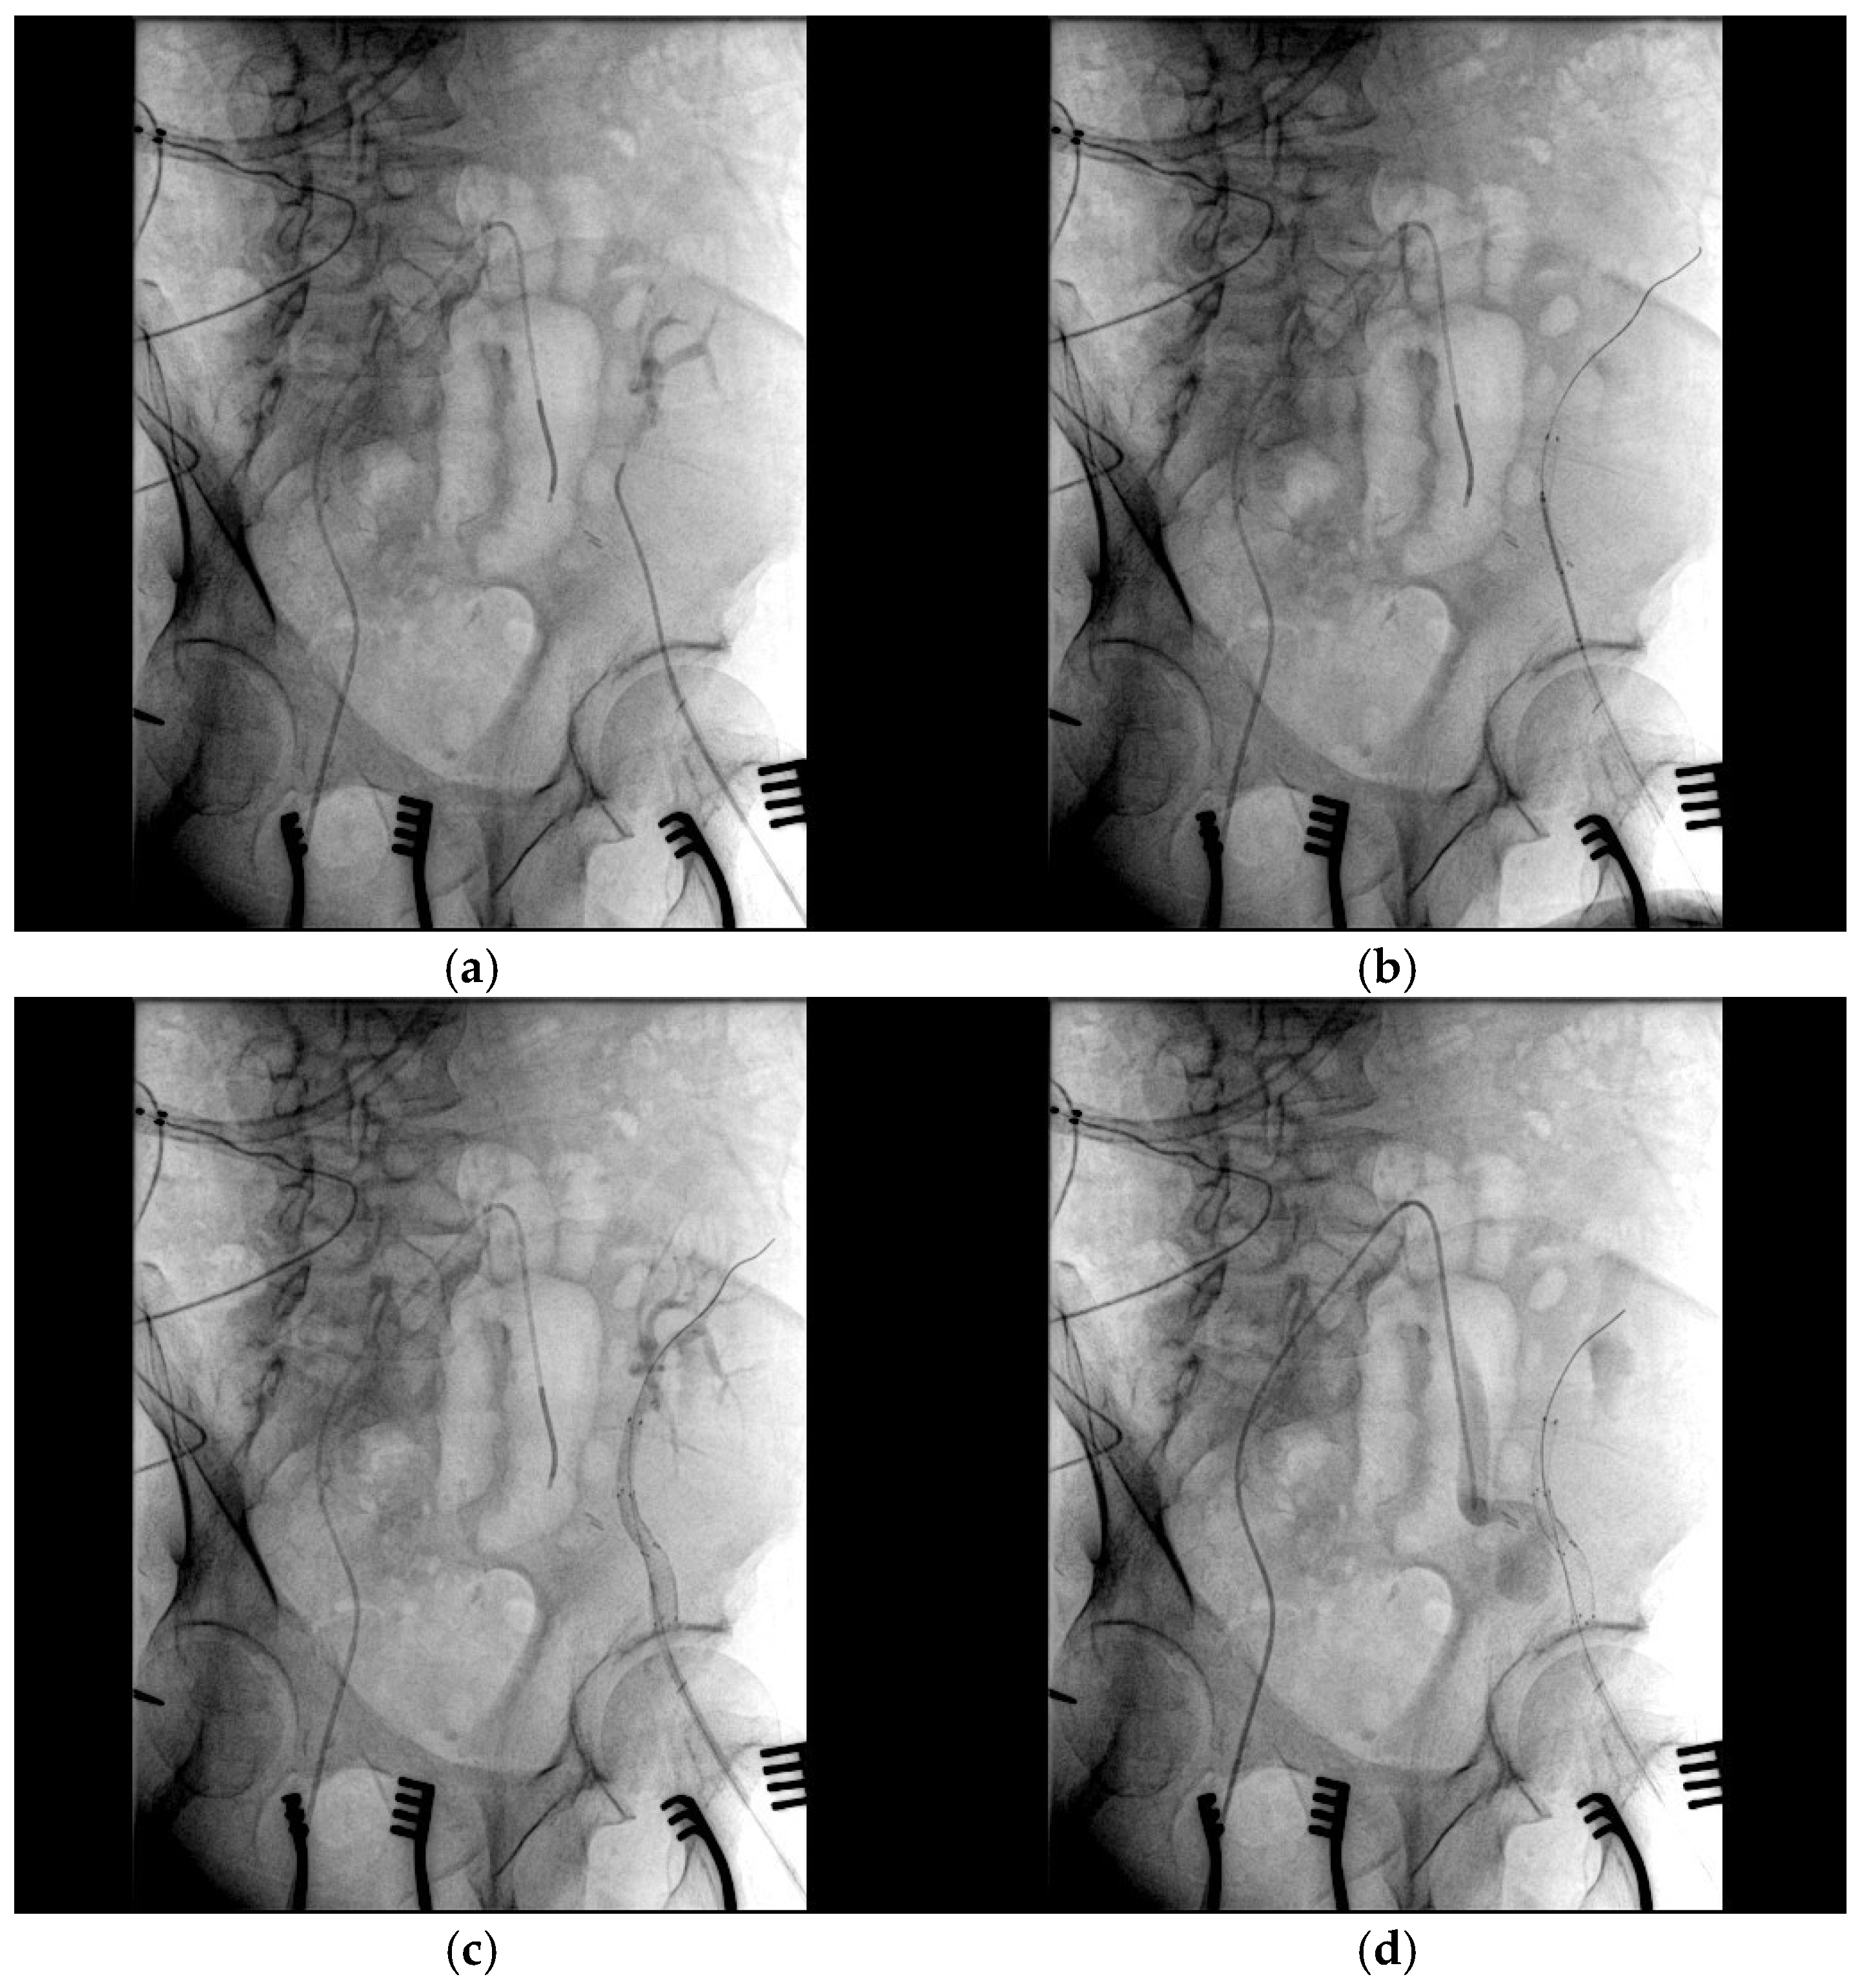

- Bypass grafting ensured continuous perfusion to the lower limb, mitigating the risk of ischemic complications;

- Endovascular stenting minimized surgical trauma while effectively excluding the pseudoaneurysm;

- Coil embolization provided an additional layer of pseudoaneurysm isolation, further enhancing treatment efficacy.